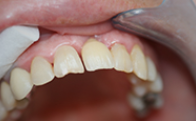

Chaque cas est unique nous essayons toujours de privilégier la meilleure solution pour le patient, d'abord d'un point de vue thérapeutique mais aussi d'un point de vue financier.

Ces cas cliniques sont une illustration pédagogique de traitements odontologiques. Leur objectif est de mettre en image des soins dentaires pour une meilleure compréhension de ceux-ci.